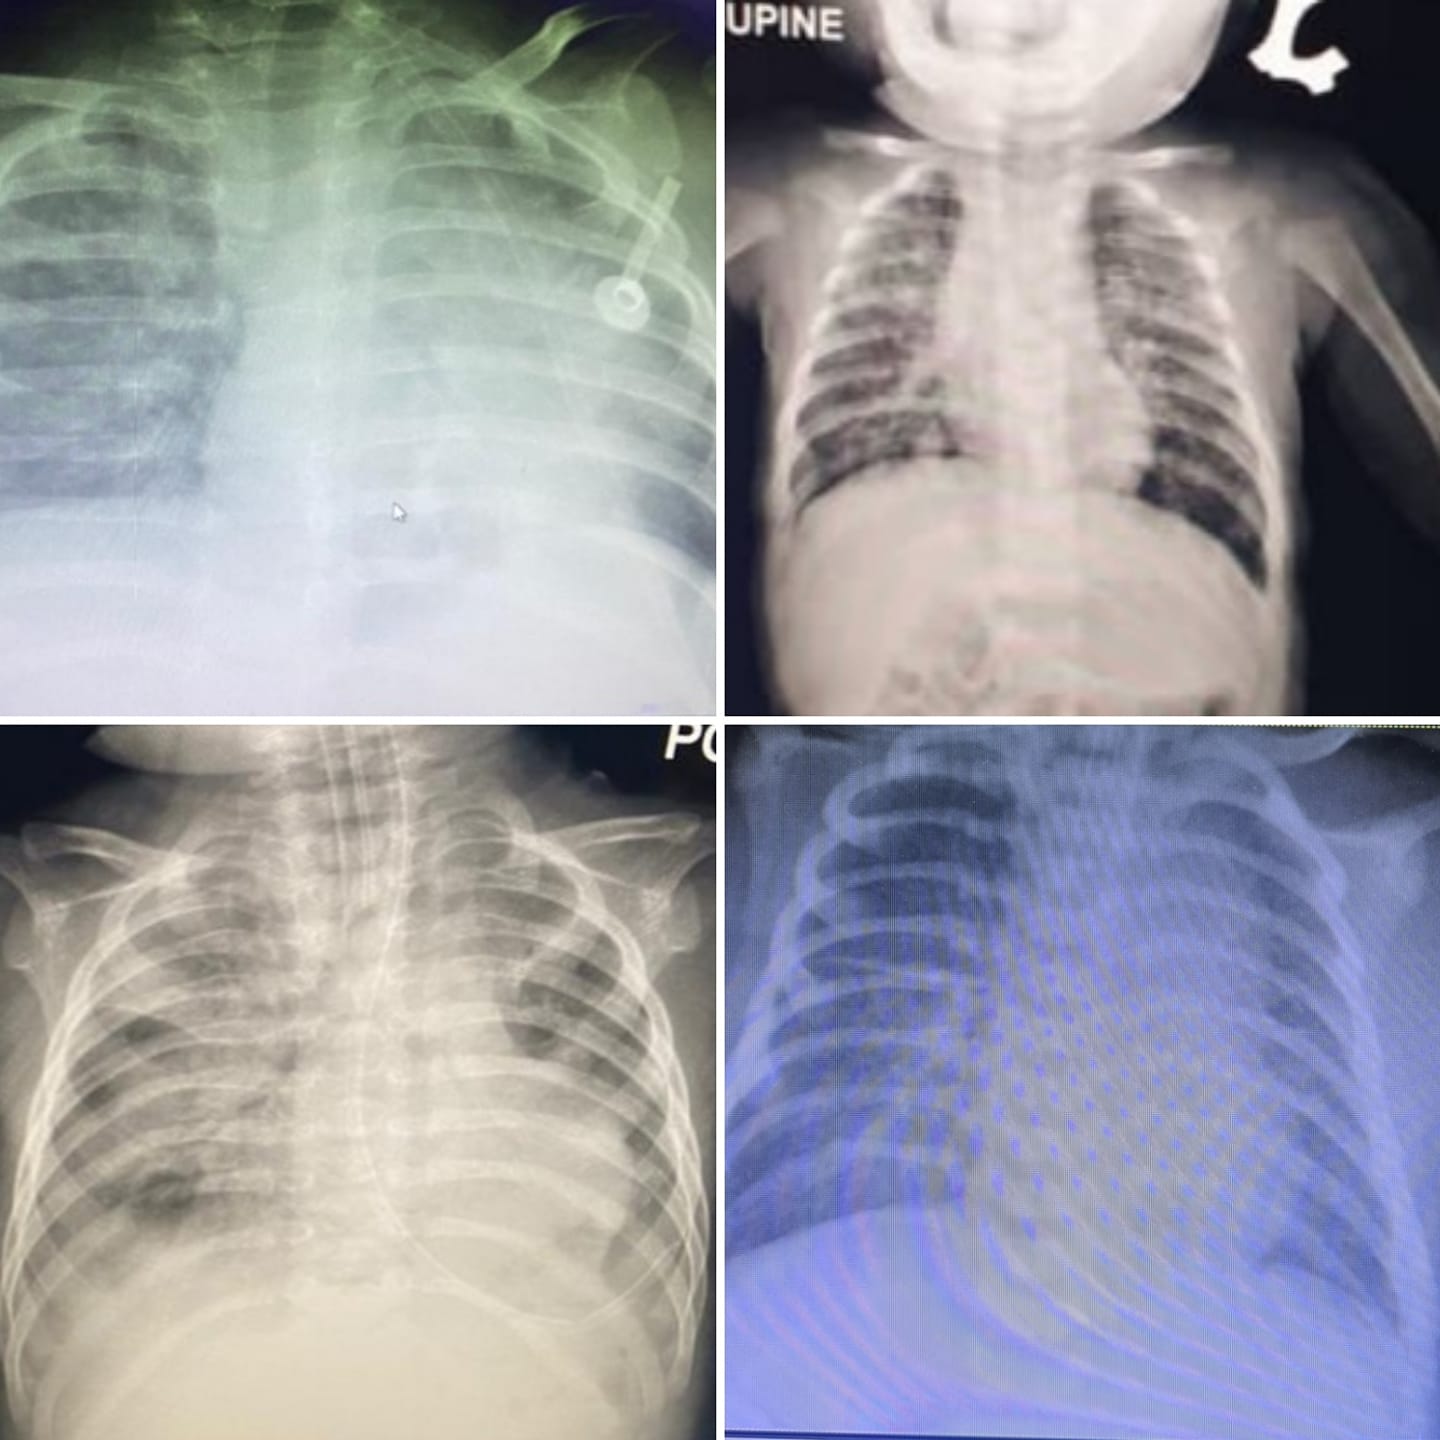

另外,哥打峇鲁苏丹后再纳二世医院儿科主任兼专科医生拉斯丹日前也在脸书发布一段视频,显示感染冠病儿童鼻子插入了呼吸辅助仪器,小小的身体吃力地呼吸。

双溪毛糯医院儿科医生茜蒂莎拉也在推特转发这段视频时表示,今年年初,儿童感染冠病后病情最严重的只有到第三阶段,即肺炎(pneumonia)不需要氧气辅助。

“但是现在变种病毒已经导致孩童的病情会达到第四和第五阶段。在吉兰丹,有的需要插管。孩子的生命是无法换回的,加上儿童并不能接种疫苗。”